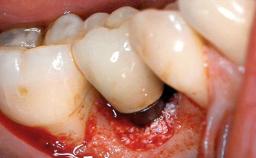

Peripheral Giant-cell Granuloma Associated with Peri-implant Tissues